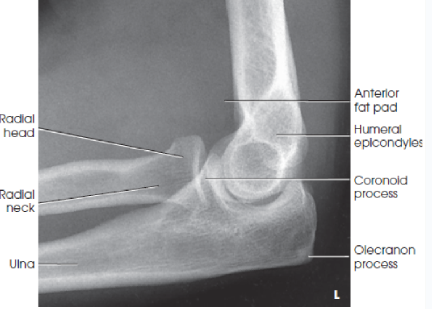

What should the part position be for a lateral elbow?

extremity in same plane with long axis parallel to IR

elbow flexed 90 degrees and placed in center IR

forearm resting on ulnar surface

wrist in true lateral

humeral epicondyles perpendicular to IR

what should be in profile for a lateral elbow image?

the olecranon process